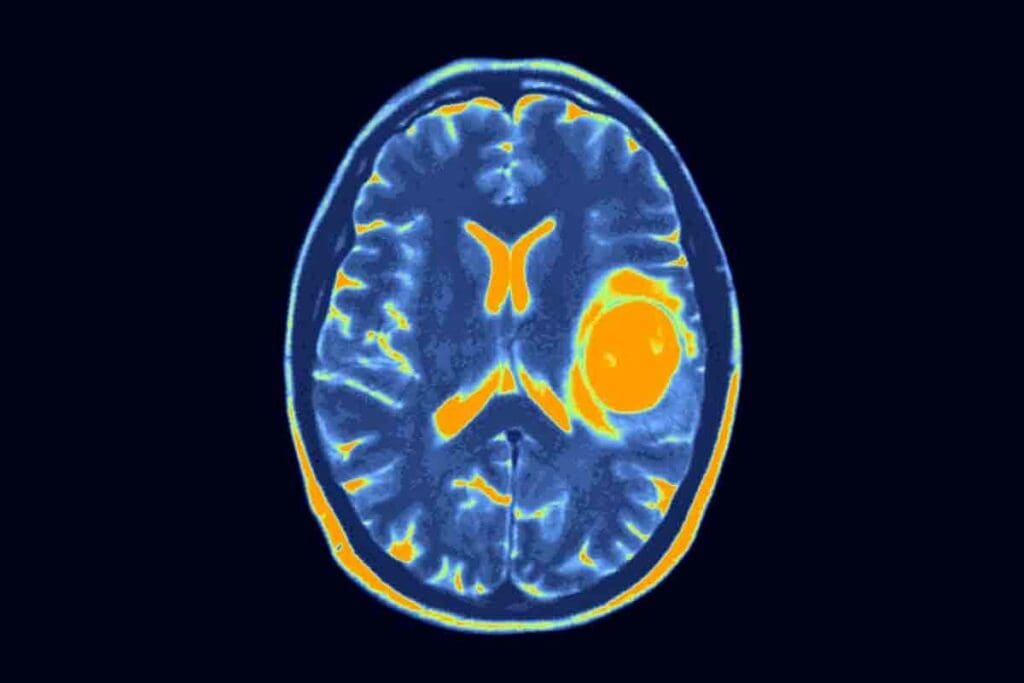

Neuroimaging Techniques

Neuroimaging is vital in diagnosing pediatric glioblastoma. We mainly use Magnetic Resonance Imaging (MRI) to see the tumor’s size and location. MRI gives us detailed images to check how the tumor affects the brain.

We also use Computed Tomography (CT) scans and Positron Emission Tomography (PET) scans to get more info. These scans help in understanding the tumor better and in staging.